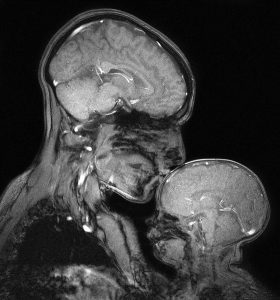

Bir anne ve çocuğun birlikte çektiği ilk MR görüntüsü bu.

Saxe nihayet planını, ikinci oğlunu doğurduktan sonra Nisan 2015’te denedi. İki gün boyunca, o ve Percy, doğru görüntüyü üretmek için birkaç saat boyunca tarandı. (MRG radyasyon kullanmıyor ve bilinen zararlı bir etkisi yok.)

Makine çok gürültülü, bu yüzden Saxe kulak tıkaçları takarken, Percy’nin kulaklarının üstünde minik yastıkları vardı. İyi çalıştılar: Gördüğünüz resimde uyuyor.

Bu, anne ve çocuğun bağını gösteren ilk manyetik rezonans görüntüsü (2015).

Bebeğin beyni daha yumuşak ve daha karanlık çünkü önemli ölçüde daha az beyaz maddeye sahip. Beyaz madde, beyninizdeki mesajları ileten tellerin yalıtımı olan miyelinden oluşyor.